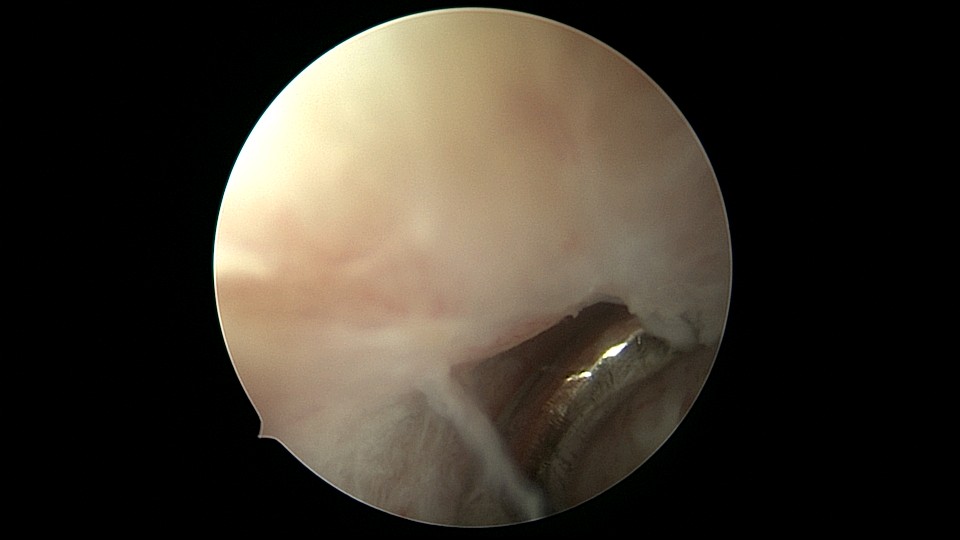

患者54岁,G1P1,剖宫产1次,安环30+年,绝经4年。40年前患者曾行左侧髋关节骨折手术,左下肢外展困难,患者肥胖,阴道很深,金属扩阴器和一次性扩阴器均无法暴露宫颈,用阴道内镜方式进入宫腔,但宫腔镜长度不够,远远能看见环,无法到达环的部位,再次试图暴露宫颈失败,用宫颈钳夹着阴道壁下拉,宫腔镜进入宫腔,但异物钳夹持力度不够,取出失败。用取环钩盲探沿宫腔镜外侧推挤进入宫腔,经历多次拧转,取环钩几乎向前弯成直角,直视下终于钩住节育环,掰直取环钩后缓慢拉出节育环,环变形。